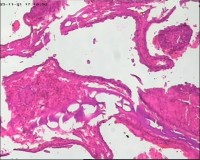

性别

女

年龄

20岁

停经3月,阴道不规则流血7天。

宫刮物

灰白灰红碎组织一堆,大小为7*6*1cm,部分组织呈水泡状

水肿的绒毛和蜕膜,没看到增生的滋养细胞。必要时可做IHC除外部分葡萄胎,并结合临床HCG。

雾蒙蒙:

需要除外一下部分性水泡状胎块可能

考虑葡萄胎